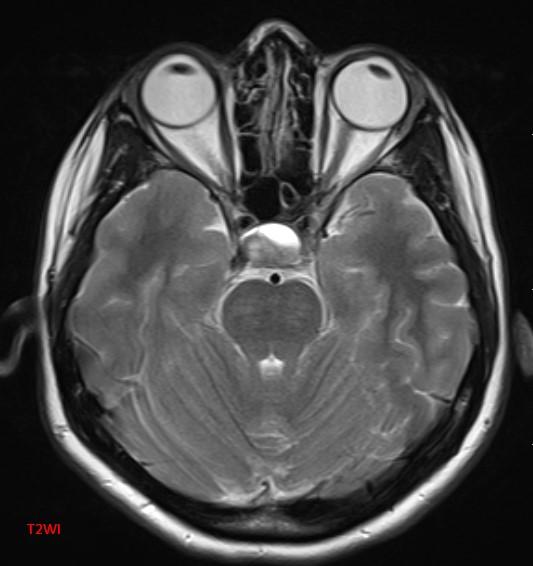

*30-year-old pregnant woman with headache and diplopia.

What is the most likely diagnosis?

Answer: Pituitary apoplexy

MR images reveal an ovoid lesion (red arrows) in the pituitary fossa with suprasellar extension. The optic chiasm is compressed (yellow arrows). The lesion is T1 and T2 hyperintense showing blood-blood fluid level (blue arrows).